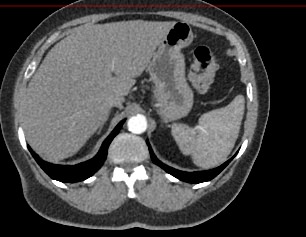

Мультиспиральная компьютерная томография селезенки – высокоинформативный лучевой метод исследования, основанный на использовании рентгеновского излучения и позволяющий детально визуализировать паренхиму селезенки, состояние близлежащих органов и тканей, питающих ее кровеносных сосудов и регионарных лимфоузлов.

МСКТ селезенки проводится как с использованием контраста, так и без него. Контрастирование применяется для выявления патологических очагов, которые могут быть не видны при нативном исследовании. Для этого внутривенно вводится контрастный препарат, содержащий йод и накапливающийся в патологических очагах опухолевой и воспалительной природы.

Мультиспиральная компьютерная томография селезенки с внутривенным болюсным контрастированием используется в диагностике гематологических заболеваний, опухолевых процессов, при планировании хирургического вмешательства и для отслеживания эффективности лекарственной терапии.